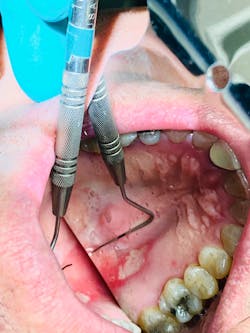

A relatively healthy 62-year-old male presented with a chief complaint of “a large sore on the roof of [his] mouth.” The patient wasThe clinical exam revealed a large 12x9 mm lesion on the right side of the junction between the hard and soft palate. It had a white center that was surrounded by an erythematous border, most notably advanced in the oral-pharyangeal direction (figure 1).